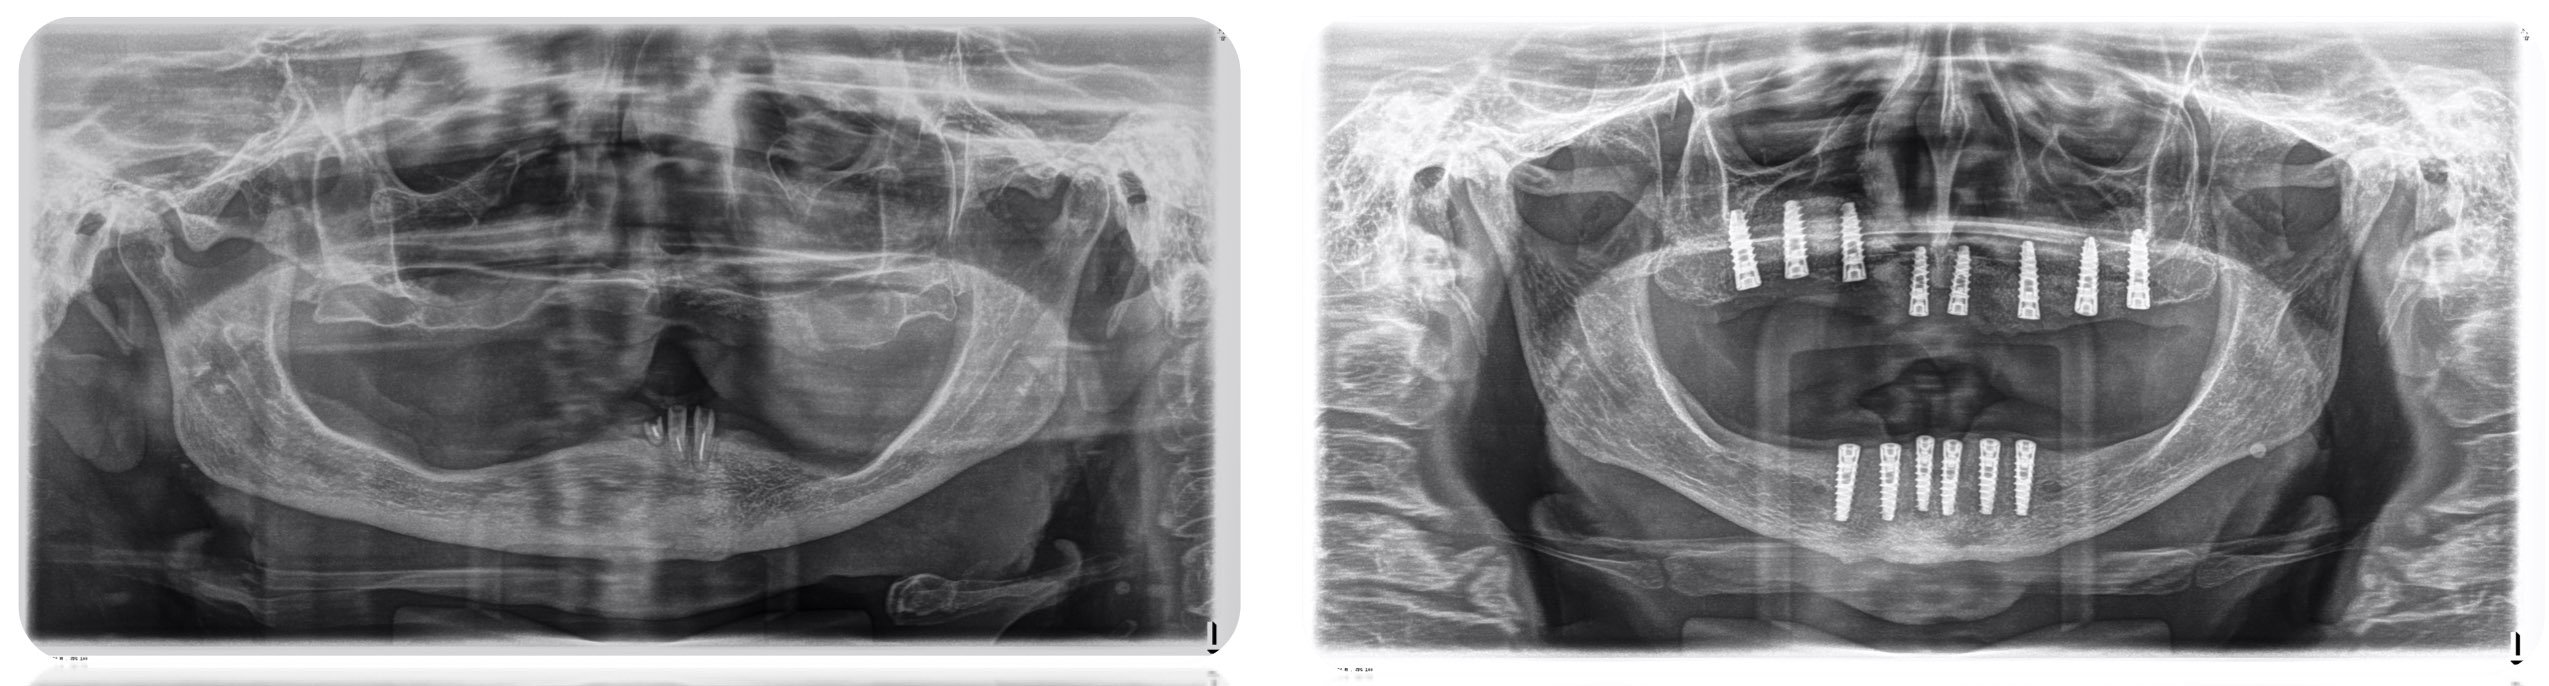

Los implantes son elementos metálicos usualmente en titanio puro que se ubican quirúrgicamente en los huesos maxilares, debajo de las encías. Una vez colocados en el lugar se puede colocar sobre ellos las coronas o puentes fijos que reemplazarán a las piezas dentarias perdidas